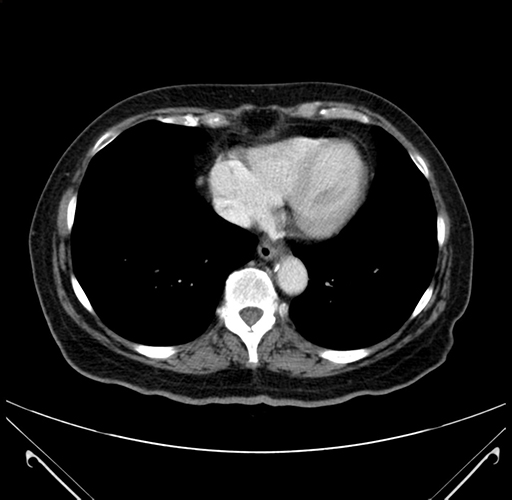

Pre-Chemo: Axial Venous

Axial Venous